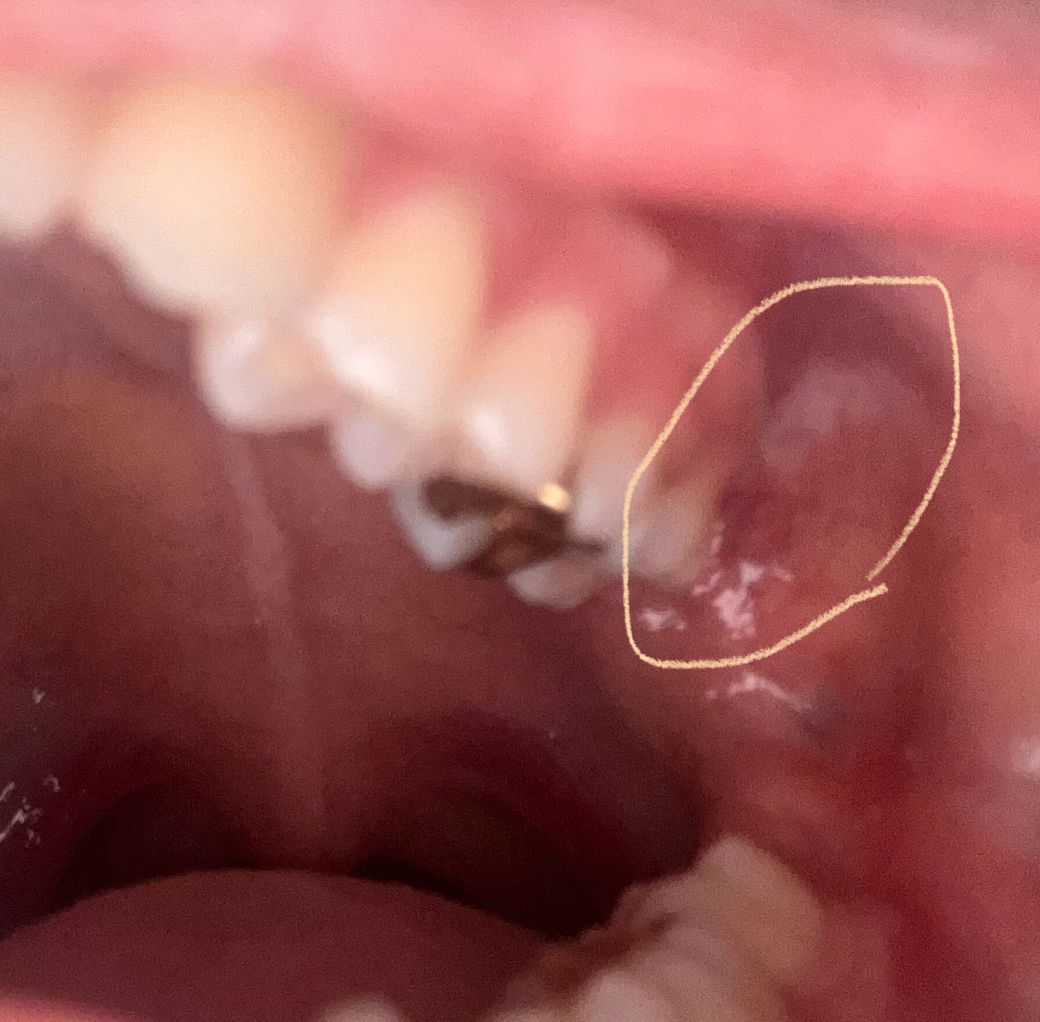

구강편평태선인가요? 어금니 뒤쪽이 빨간 핏줄들이 잘보이고 하얗게 됐습니다

구강편평태선인가요 오른쪽은 조금 하얗긴한데 핏줄도 잘 보이지않는데 왼쪽 어금니뒤쪽은 핏줄들도 너무 두드러지게보이고 그쪽이 하얗게 됐습니다 그물모양은 아닌것같은데 선처럼 쭉 되어있습니다

사진상으로 보이는건 편평태선은 아니고 볼살이 치아에 눌렷거나 자극을 받아서 생긴 자국같습니다.

편평태선은 다양한 양상이 나타날 수 있습니다 편평태선 외에도 구강 내 병소가 의심되니 구강내과가셔서 조직검사를 받아보시면 좋을 것 같습니다